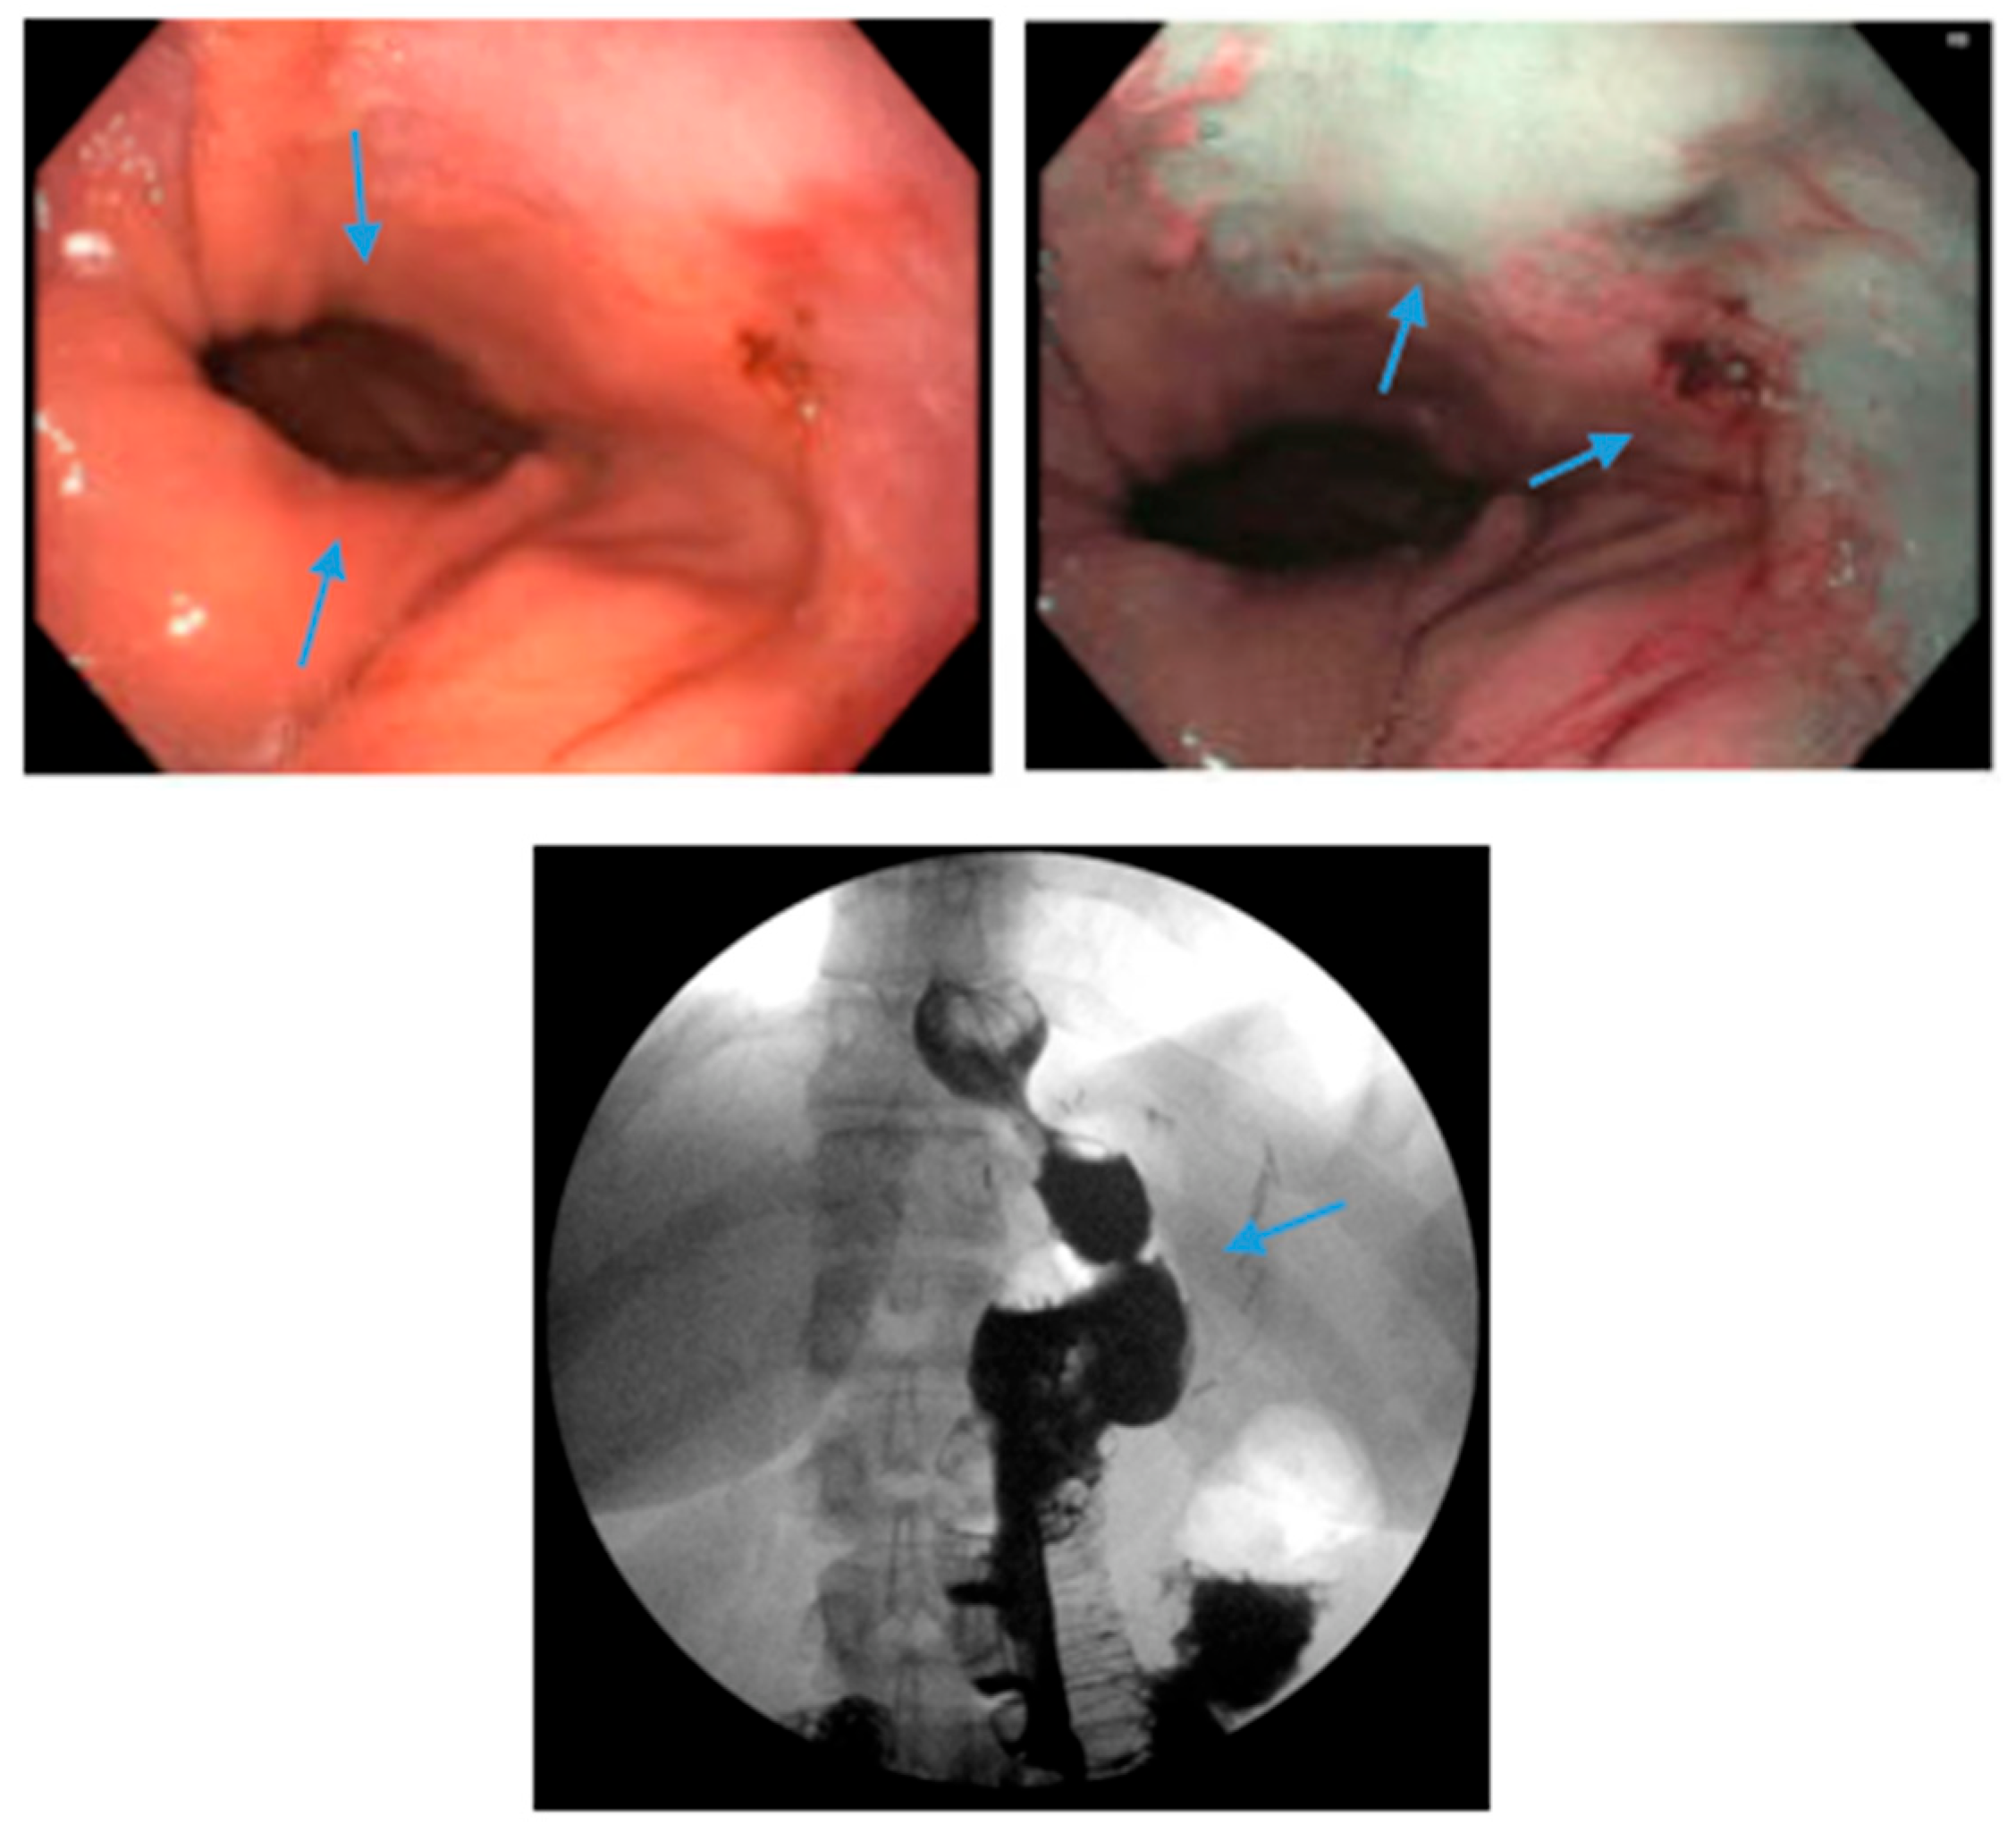

Figure 6.

Endoscopic images reveal a 3 cm hiatal hernia (arrows, top left) and Los Angeles Grade B esophagitis (arrows, top right) in the lower third of the esophagus with narrow-band imaging in a patient post-sleeve gastrectomy with symptoms of gastroesophageal reflux disease. The patient eventually required Roux-en-Y gastric bypass (arrow, bottom) and concomitant hiatal hernia repair, as demonstrated on upper gastrointestinal series.

Conversion from SG to RYGB is ultimately necessary for some patients with refractory GERD post-SG (Figure 6). There are robust data that conversion to RYGB is very effective for the treatment of GERD, as detailed in Table 2, in addition to its beneficial effects on weight loss and other comorbidities (i.e., diabetes, hypertension, dyslipidemia). In a recent retrospective study by MacVicar et al., 4412 patients required revisional surgery due to GERD, which comprises 24% of all conversion procedures [71]. SG was the original surgery in 80.1% of cases and Roux-en-Y was the revisional surgery in 84.4% of cases [71]. However, conversion from SG to RYGB is not without additional risk. In a recent study with matched cohorts of 5912 patients, an increase in re-admissions, intervention, conversion to open surgery and operative time was documented in the group which underwent conversion from SG to RYGB compared to primary RYGB. There were no significant differences in mortality or complications noted between the two groups. In a study by Dang et al., conversion from SG to RYGB compared to primary RYGB was associated with an increased rate of serious complications (7.2% vs. 5%, p < 0.001), including anastomotic leaks, bleeding and reoperation, although no significant difference in mortality between the two groups was demonstrated in the study [72].

Many studies reveal significant improvement in GERD symptoms and the use of acid suppression medications following conversion to RYGB. Studies by Langer et al. and Gautier et al. both reported that all patients were able to discontinue acid suppressive medications [73,74]. Parmar et al. revealed that 80% of patients discontinued acid suppressive medications whereas Hendricks et al. documented that 75% of patients had a complete resolution of GERD with conversion to RYGB [75,76]. A study by Strauss et al. concluded that 80.2% of patients who underwent conversion to RYGB had improvement in GERD symptoms [77].

The average rate of conversion from SG to RYGB due to GERD is approximately 5–10% [26,30,78]. In the SLEEVEPASS trial, the rate of conversion to RYGB was noted to be 6% [78]. In the SM-BOSS trial, the reported rate of conversion to RYGB was 9% [26]. In a meta-analysis of 46 studies by Yeung et al., 4% of patients underwent conversion to RYGB [30]. In a review of 73 cases, Langer et al. reported a conversion rate of 11% [73]. Some studies report a higher rate of conversion, although these studies had limitations [75,77,79].